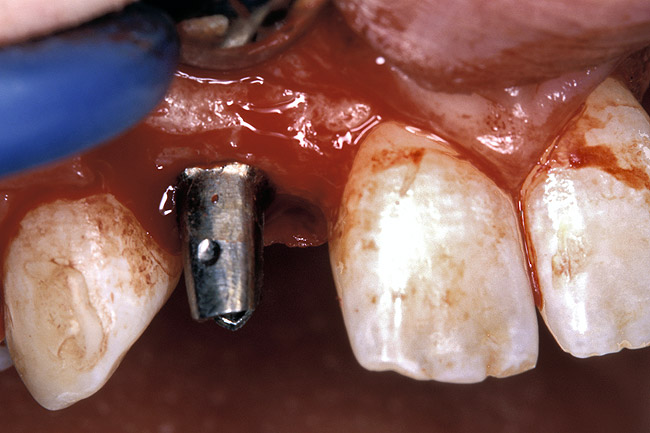

Periapical radiographs were taken to help determine the mesial-distal inclinations of the adjacent tooth roots (Figure 1). The radiographs revealed a serious issue, convergent roots for the right canine and right central, which eliminated that area as a potential implant-receptor site. The space between the left central and canine teeth was minimal, although the roots were relatively parallel. Clinical examination (manual palpation of the root eminences superiorly to the vestibule on the right side) confirmed the root convergence (Figure 2A). The flat, wide zone of the keratinized tissue and lack of interdental papilla was evident for the missing right lateral incisor. There was a marked difference in clinical appearance for the left lateral, which could impact the eventual plan of treatment (Figure 2B). Other significant clinical findings included bilateral facial bone concavities, which existed as a result of the congenitally missing tooth roots. As a diagnostic cue to the underlying bone topography, it is important to follow the demarcation between attached and unattached gingival tissue, and note the crestal width of the available keratinized tissue (Figure 2C).

Figure 2a  Pretreatment buccal views showed (A) root convergence, (B) a difference in clinical appearance of the left lateral, and (C) significant crestal width of keratinized tissue.

Figure 2a